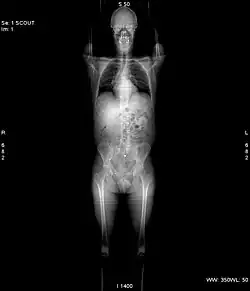

Vor jeder Aufnahme wird grundsätzlich eine Übersichtsaufnahme aufgenommen. Hierbei steht die Röntgenröhre still. Der Patient wird mit Hilfe des verfahrbaren Tisches am Fächerstrahl der Röhre vorbeigefahren. Im Ergebnis erhält man ein Bild, das einer klassischen Röntgenaufnahme sehr ähnlich sieht. Dieses Bild dient jedoch nur der Planung anschließender Aufnahmen.[1]

Bis Mitte der 1990er Jahre war die rein axiale Aufnahme die einzig mögliche Aufnahmeart. Die Röhre drehte sich bei still stehendem Tisch um eine volle 360°-Drehung um den Patienten. Im Anschluss wurde der Tisch verfahren und die nächste Schicht aufgenommen. Jeder klinische CT verfügt bis heute über diesen Modus, da er ein besseres Schichtempfindlichkeitsprofil und damit eine bessere Detailerkennbarkeit bietet. Er wird allerdings mittlerweile selten eingesetzt.[1]